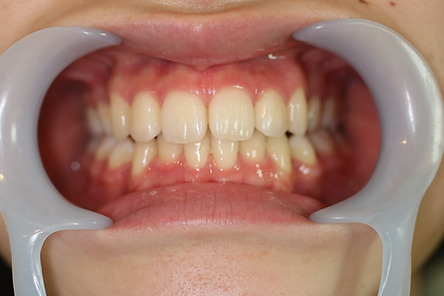

1矯正・マウスピース【治療例2】

治療後